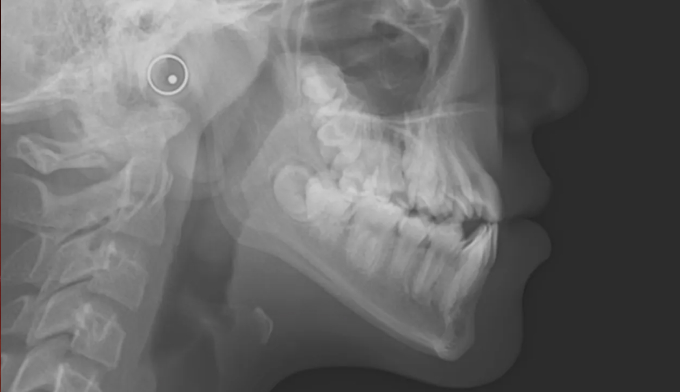

너무 늦은나이에 교정치과를 찾아서 아쉬운 경우입니다.

너무 좁은 위턱 공간으로 인해 치아의 맹출 순서가 어긋나버렸습니다.

송곳니가 원래 나와야 할 공간이 없다보니 작은 어금니 위치로 이동해서 맹출하고 있습니다. 이를 치아 전위라고 합니다.

이와 더불어 좁은 위턱 악궁은 얼굴 전체의 비대칭을 유발하고 있고, 아래턱의 과성장은 주걱턱 경향까지 보이고 있습니다.